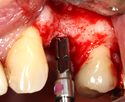

Basic implant surgical procedure

The area of the mouth that is missing a tooth is identified.

An area with a single missing tooth

An incision is made across the area and the flap of gingiva is opened to show the bone of the jaw.

An incision is made across the gingiva, and the flap of tissue is reflected to show the bone of the jaw.

A series of slow-speed drills create and gradually enlarge a site in the jaw for the implant to be placed. The hole is called an osteotomy.

Once the bone is exposed, a series of drills create and gradually enlarge a site (called an osteotomy) for the implant to be placed.

The implant fixture is turned into the osteotomy. Ideally, it is completely covered by bone and has no movement within the bone.

A healing abutment is attached to the implant fixture and the gingiva flap is sutured around the healing abutment.

A healing abutment is attached to the implant fixture, and the flap of gingiva is sutured around the healing abutment.